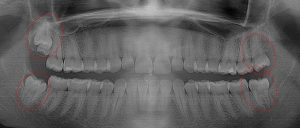

This 19 year old patient has all four 3rd molars present (circled). Only the upper left 3rd molar has fully erupted. The lower left 3rd molar is partially exposed and decaying while the lower right soft tissue impacted, both requiring extraction. Note the double crown on the upper right third molar.